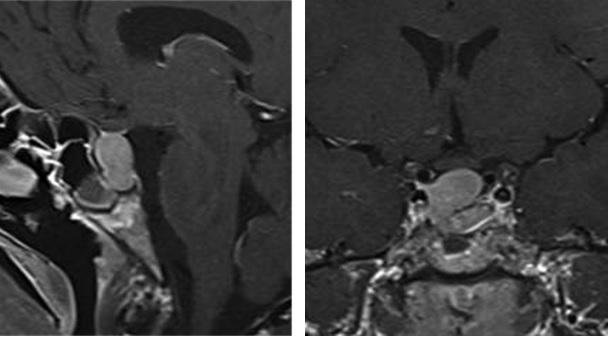

西门子MAGNETOM Aera 纪元四度磁共振可进行神经系统、脊柱、四肢关节、腹部、心脏、血管等全身各个系统的不同疾病的检查,而且能进行波谱分析,对肿瘤的性质鉴定有很高临床价值。对CT无法发现的超早期脑梗塞病变具有无可替代的作用,能发现发病后几分钟内的病灶,为挽救患者生命和改善预后、减少致残率赢得时间。

CASE 3: 胸椎肿瘤(金属植入物)